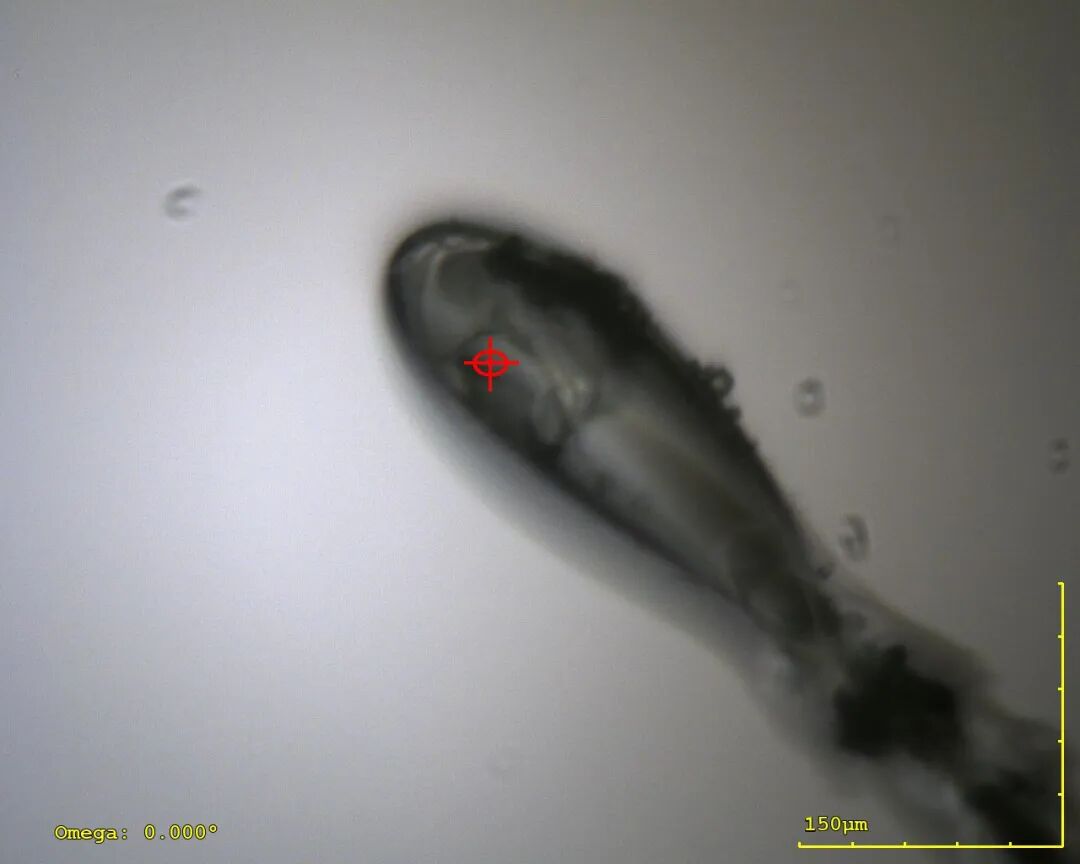

▶ 结晶和结构解析(周期:1-2周)

*客户结果据保密协议无法展示,替换为相似分子量自研MALT1蛋白

人源ALDH2结构示意图